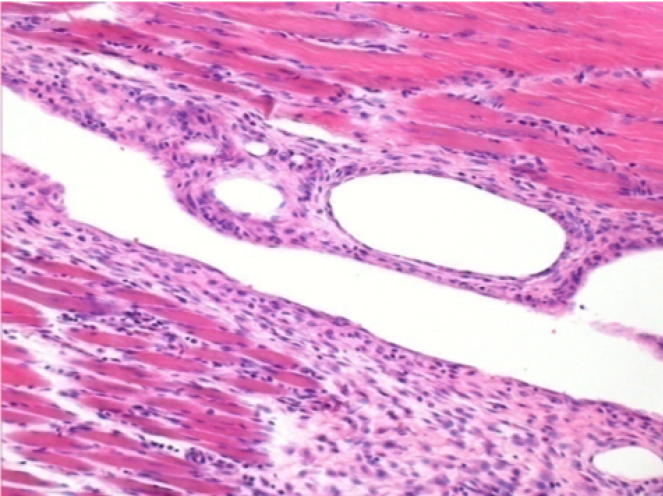

Через 10 днів після ін'єкції Ендопіл 0,1 мл в правий претибіальний м'яз.

Тут можна побачити утворення вакуолей, які оточені лімфоцитами. Вакуолі відрізняються від некрозу тканини. Присутність лімфоцитів пов'язана з проникністю клітинних мембран.